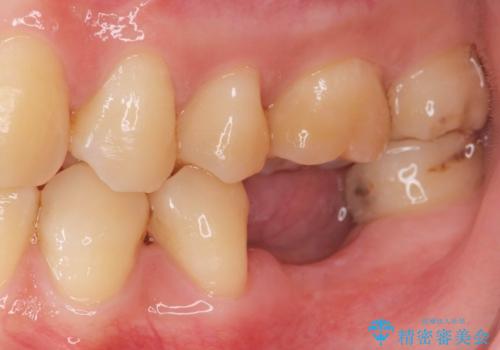

大臼歯の欠損 インプラント治療

- 左下大臼歯が噛みしめにより割れてしまい、抜去後のインプラント治療を希望され来院されました。

しっかりと咬合負担能力の増えるインプラントによる欠損補綴を計画します。